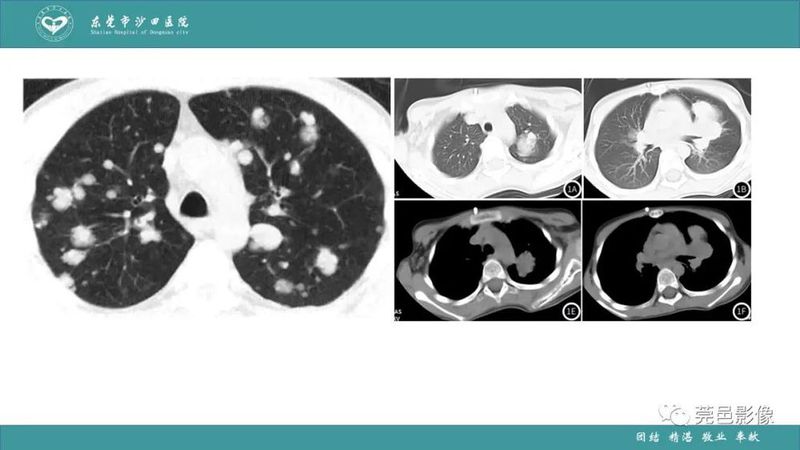

「肺炎克雷伯杆菌肺炎」影像学诊断+鉴别诊断